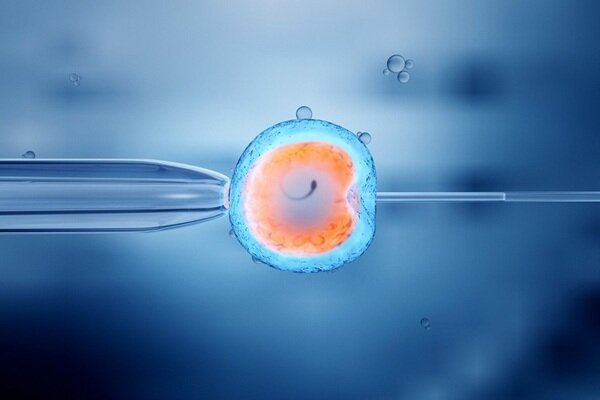

خانم دکتر به عنوان سوال اول درباره مراحل کار یک جنین شناس در فرایند IVF برایمان بگویید.

در فرآیند IVF، برای هر تخمک خانم، یک اسپرم مناسب زیر میکروسکوپ توسط جنینشناس انتخاب میشود؛ گاهی این انتخاب به دلیل کیفیت پایین اسپرم ساعتها زمان میبرد. برخی آقایان ممکن است میلیونها اسپرم داشته باشند، درحالیکه در برخی موارد حتی یک اسپرم هم یافت نمیشود. در چنین شرایطی، اورولوژیست با انجام عمل «تِسه» (TESE) مستقیماً از بیضه اسپرم استخراج میکند.

در شرایط عادی، اسپرم استخراجشده با معیارهای دقیق جنینشناسی انتخاب و به درون تخمک تزریق میشود (میکرواینجکشن). سپس جنینهای تشکیلشده برای چند روز در دستگاههای خاص کشت و پایش میشوند. در این مرحله، کیفیت تخمک و اسپرم اهمیت فراوانی دارد. مصرف دخانیات و الکل میتواند تأثیر منفی مستقیم بر کیفیت تخمک و جنین داشته باشد و باعث تشکیل جنینهای ضعیف یا غیرسالم شود.

در فرآیند IVF، پس از تشکیل جنین، در برخی موارد لازم است تست تعیین سلامت جنین (PGT-A) انجام شود. در این مرحله، نمونهای از سلولهای جنین (با روش بیوپسی) جدا شده و برای بررسی ژنتیکی به آزمایشگاه ژنتیک ارسال میشود. نتایج این بررسی نشان میدهد که آیا جنین از نظر کروموزومی سالم است یا خیر. تنها جنینهای سالم برای انتقال به رحم مادر انتخاب میشوند.